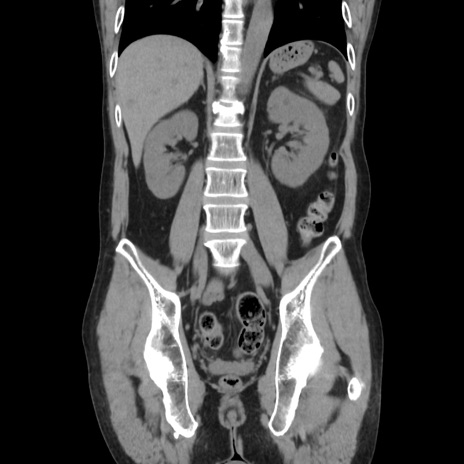

症例37(冠状断像)

【症例】40歳代 男性

【主訴】腹痛

【現病歴】4時間ほど前に電車に乗車中に臍部上より腹痛出現。徐々に増悪し起立困難となり、救急外来受診。生ものは数日食べていない。今朝お雑煮を食べた。

【身体所見】BT 36.8℃、BP 117/84mmHg、HR 91/min、SpO2 97%、苦悶様、腹部:臍上部広範囲圧痛あり、反跳痛±

【データ】WBC 8100、CRP 0.03